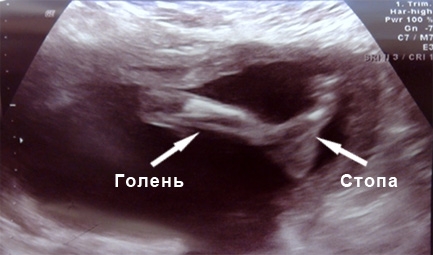

На этой неделе продолжается измерение тех же фетометрических показателей, что и на 20-й неделе беременности. На ультразвуковом исследовании можно заметить, что ноги плода стали длиннее. Это приводит к более гармоничным пропорциям его тела. В данный момент проводятся измерения всех внутренних структур плода.